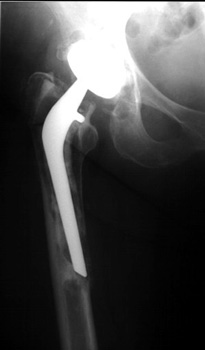

FEMORAL STEM POSITION

• Varus positioning

Varus Normal Valgus

Varus